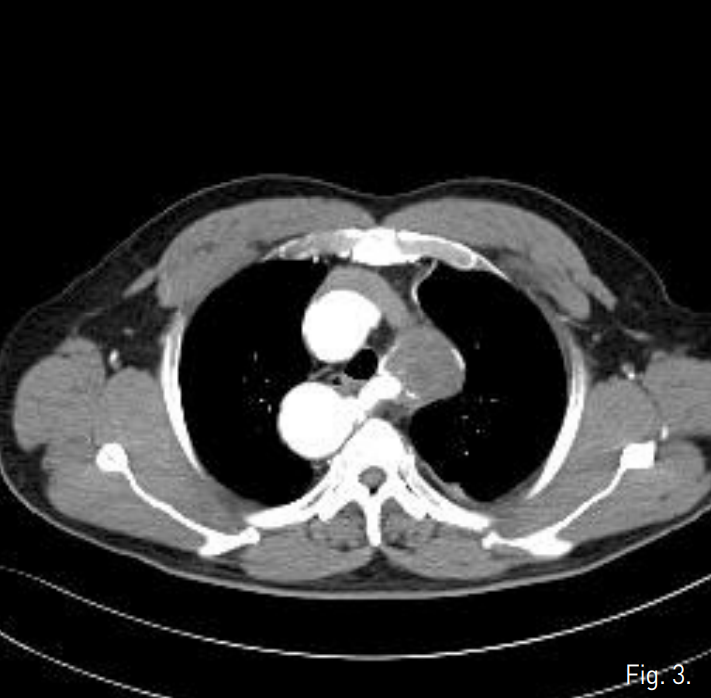

Endovascular repair 시술 후 1년 6개월 뒤 증상없이 추적검사로 시행한 조영증강 흉부 CT에서 aberrant left subclavian artery에 삽입한 stent-graft의 내강에서 aneurysm sac로 나가는 endoleak이 발견됨 (Fig. 1). Aneurysm sac의 크기는 변화 없었음.

Fig. 1

Contrast-enhanced axial CT scan shows the stent graft along the aberrant left subclavian artery. A large aneurysm with mural thrombosis is noted at the anterolateral aspect of the stent-graft, suggesting endoleak.